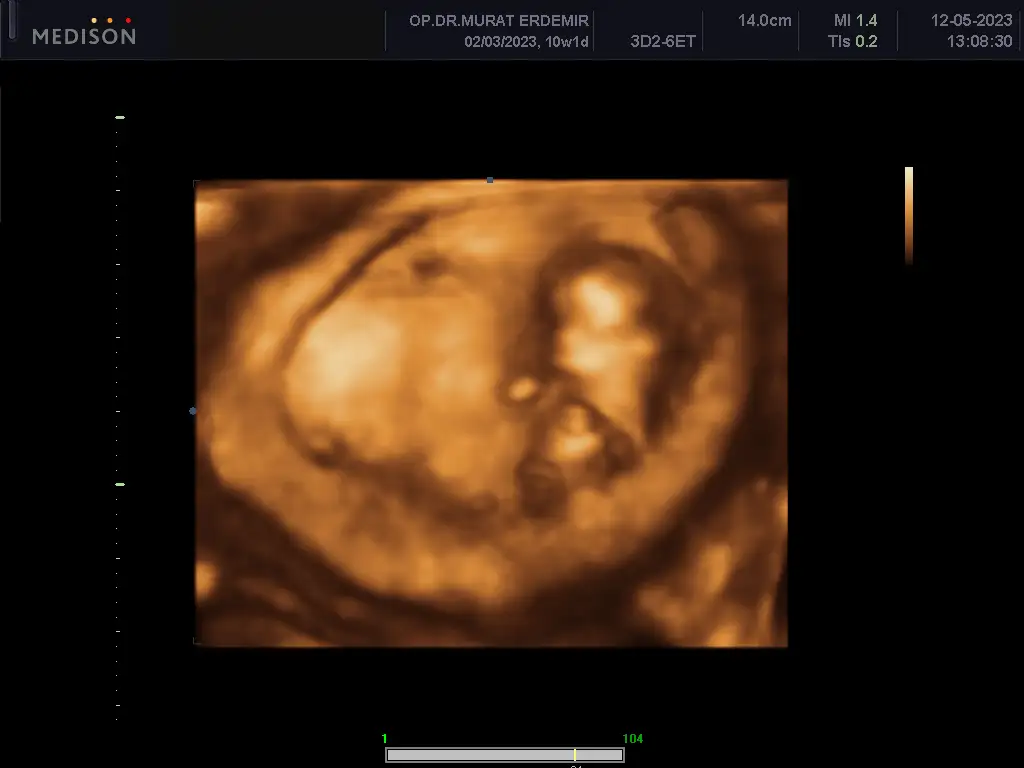

Merhaba arkadaşlar. Bugün koyu renkli kanamadan dolayı acile gittim. Bebek 10+6 olmuş. Kalp atışları da iyiydi. Rahimde bir şey görünmüyor. Ama ilk defa böyle koyu kırmızı kan gördüm. Benim durumda olan var mı? Dualarınızı bekliyorum...

Eklentiler

• IMG_20230512_155722.webp

IMG_20230512_155722.webp

23 KB · Görüntüleme: 60

Benim ilk defa oldu hocam, ultrasonda da birşey görünmedi. Kalp atışı da iyi dedi. Korkulacak birşey yok dedi ama içimiz hiç rahat değil :(

Benim ilk defa oldu hocam, ultrasonda da birşey görünmedi. Kalp atışı da iyi dedi. Korkulacak birşey yok dedi ama içimiz hiç rahat değil :KK43:

Ultrasonda kanama alanı görünmemesi ilginç .bana kanaman pıhtılı ve parça vs olursa sıkıntı demişti doktor. sonrasında 1.5 ay progestan kullandım ağızdan ve vajinal fitil şeklinde .kahverengi lekelenme şeklinde devam etti ve tamamen geçti.